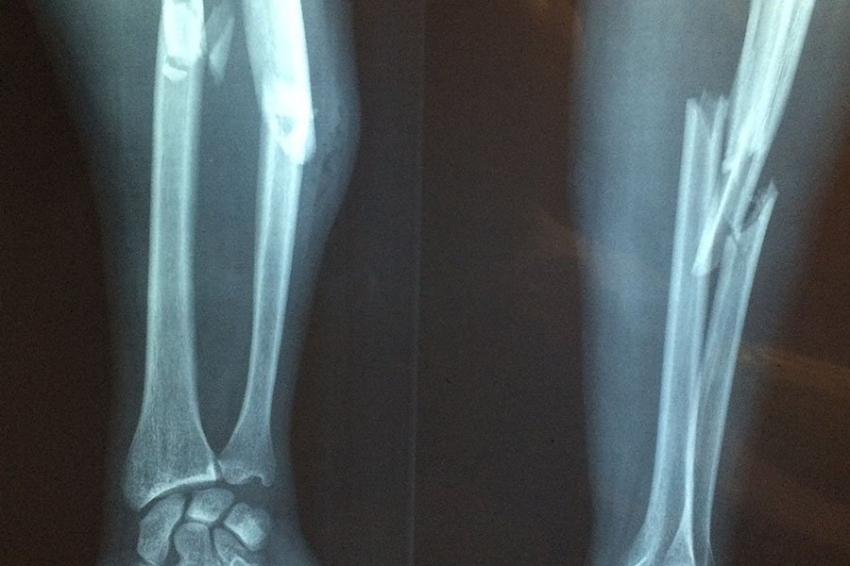

Программа профилактики падений и переломов внедряется во всех регионах страны, в том числе в Республике Северная Осетия-Алания. Участники мероприятия обсудили, что необходимо выявлять пациентов с риском переломов, оценивать эти риски и формировать группы, требующие особого внимания.

«Остеопороз – одно из наиболее распространенных заболеваний костно-мышечной системы среди лиц пожилого возраста, приводящее к снижению прочности кости.», – отметила Наталья Торопцова, заведующая лабораторией остеопороза НИИ Ревматологии им. В.А. Насоновой.